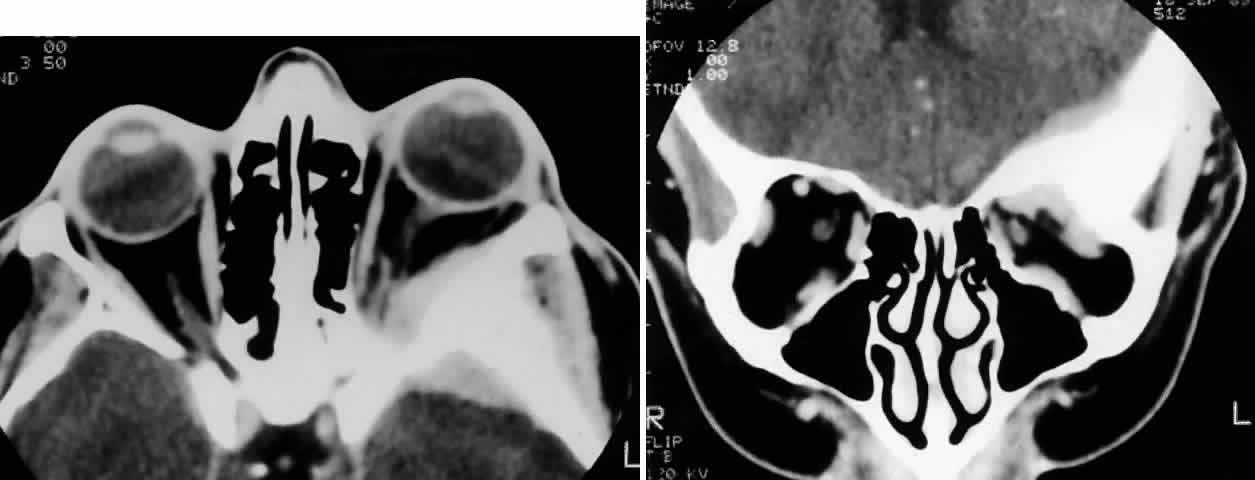

Fig. 2. A 32-year-old woman presented with a 1-month history of sinus congestion and nasal obstruction unresponsive to antibiotics. In the 1 week preceding the initial exam, the right eye became progressively more prominent and showed tearing and redness. On examination, there was mild edema of the lower lid and dysesthesia in the distribution of cranial nerve V2, and the globe was displaced 6 mm laterally and 5 mm anteriorly. There was mild limitation of abduction, chemosis, and nasal choroidal folds. An axial CT scan revealed a diffuse, destructive soft tissue mass centered in the superior nasal passage and ethmoid sinuses extending into the right orbit in contiguity with the medial rectus (A). On enhanced coronal view, the tumor was noted to involve the right maxillary antrum and to extend superiorly into the anterior cranial fossa (B). Biopsy of the sinus (C) revealed an alveolar-type rhabdomyosarcoma (muscle stain, × 320).